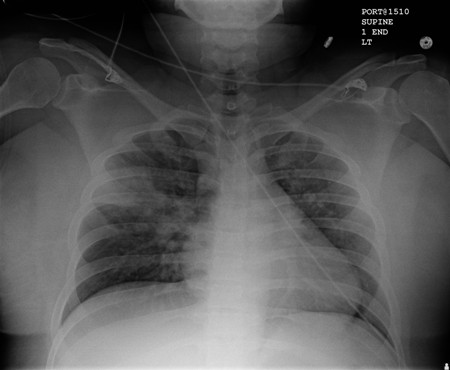

Portable chest x-ray with bibasilar opacities, worse on the right than the left, in a patient with hospital-acquired pneumonia

From the personal collection of Dr F.W. Arnold, Division of Infectious Diseases, Department of Medicine, University of Louisville School of Medicine